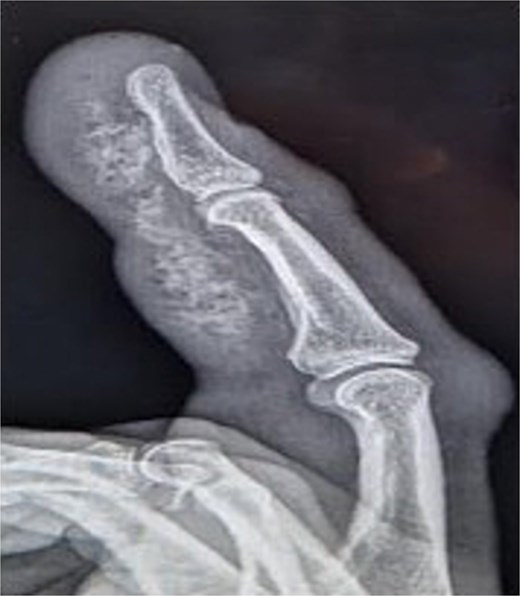

Initial presentation (Fig. 7) with accompanying X-ray (Fig. 8). Final image shows patients digit when he represented 2 months after original insult with a swollen finger and pus exudate (Fig. 9).

Image of patient three, showing his digit at presentation displaying small puncture wound on volar surface.

X-ray image of patient three showing injected material into surface of his digit, more obvious in the proximal portion.

Patients three’s digit when he represented 2 months after original insult with a swollen finger in a flexed position and pus exudate.